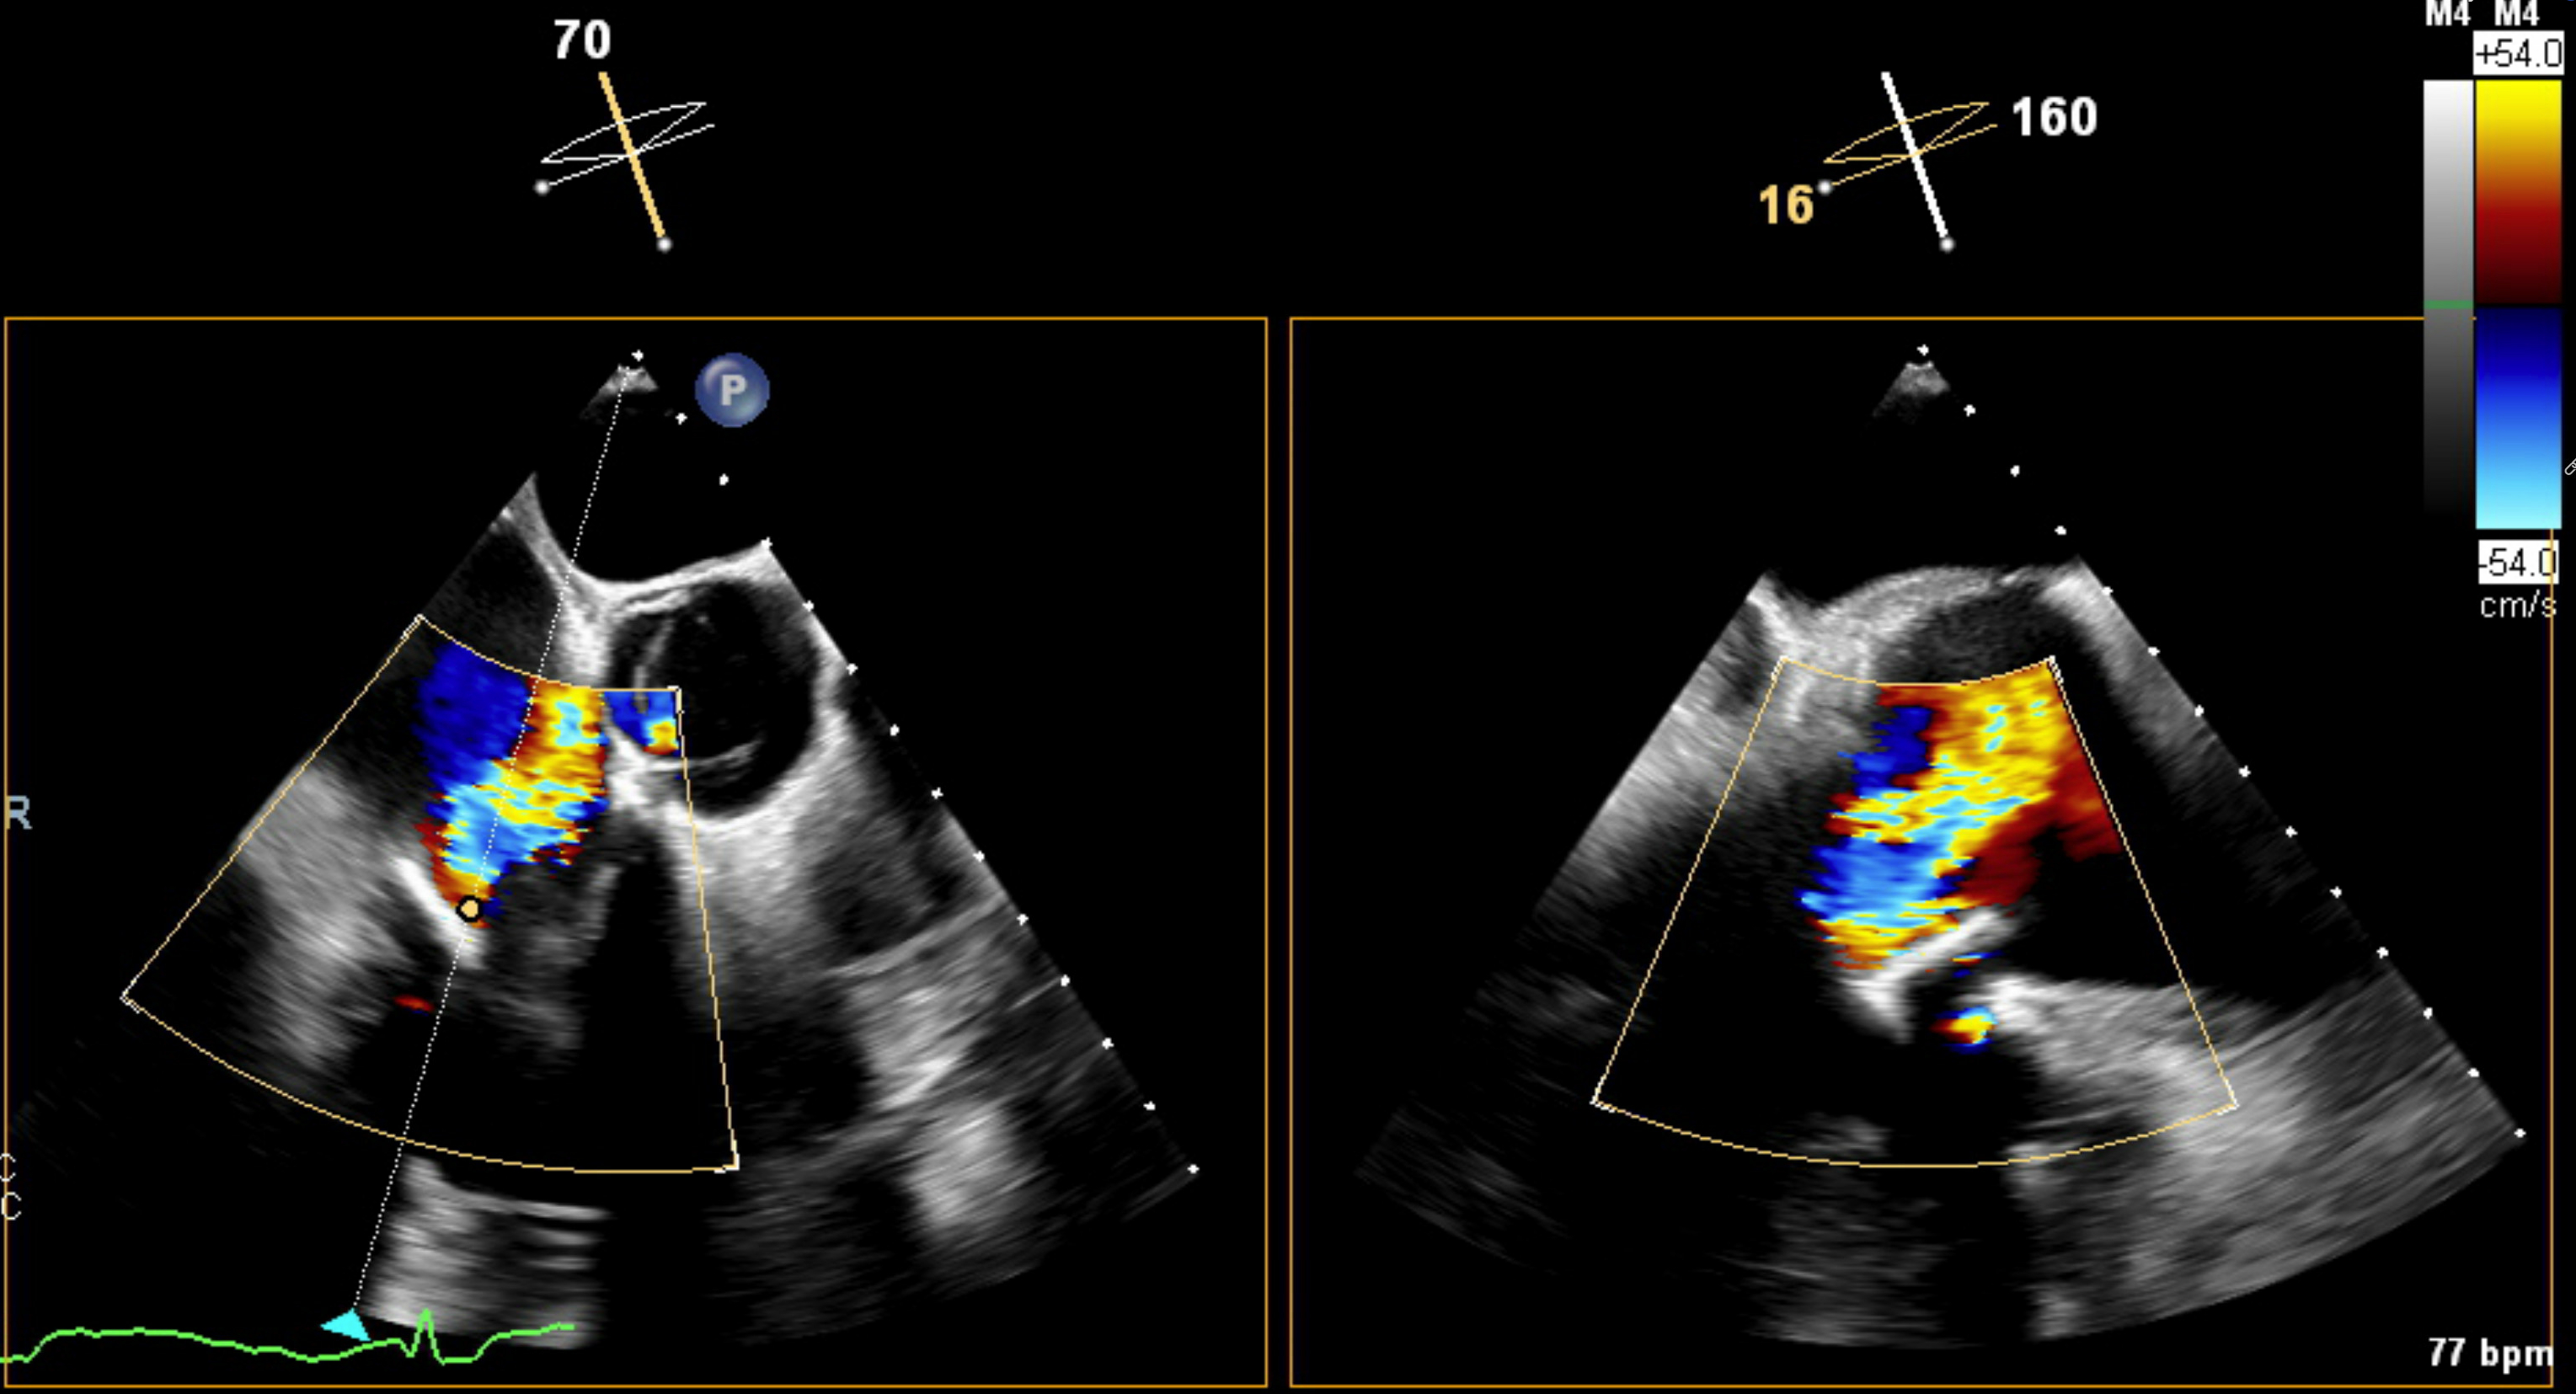

Case: A 53-year-old woman presented with acute dyspnea and orthopnea two months after a 33-mm Mitris Resilia tricuspid valve replacement for severe tricuspid regurgitation. Her history included mild aortic insufficiency and non-obstructive coronary artery disease. Transthoracic echocardiography revealed a large pericardial effusion with tamponade physiology, necessitating urgent pericardiocentesis. Transesophageal echocardiography demonstrated early SVD of the bioprosthetic valve, with poor leaflet coaptation, a central coaptation gap, and restricted anterior leaflet mobility. Extensive evaluation excluded infectious and autoimmune etiologies: blood cultures, inflammatory markers, viral serologies, thyroid function, and pericardial fluid cytology were unremarkable. Despite pericardial drainage, right atrial pressures remained elevated (mean 19 mmHg) on repeat right heart catheterization. Following a comprehensive heart team evaluation, a 29-mm Edwards Sapien valve was deployed via right internal jugular venous access within the failing surgical valve under fluoroscopic and echocardiographic guidance. Intraprocedural TEE demonstrated immediate reduction of tricuspid regurgitation severity to trace with a mean gradient of 1 mmHg. The patient had an uncomplicated recovery and was discharged the following day.